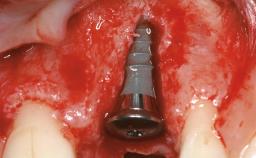

Mauricio Araujo and Flauvia Matarazzo present this straightforward clinical case, demonstrating the potential effect of implant placement depth on the resolution of peri-implant treatment. A 42-year-old systemically healthy female patient, a non-smoker with no history of periodontitis, was treated at the Dental Clinic at the State University of Maringá, Brazil between 2008 and 2009, when she received five implants restored with single crowns at sites 14, 26, 27, 36, and 46. After delivery of the implant-supported prosthetic restorations, the patient was enrolled in the supportive peri-implant therapy (SPiT) maintenance program at the same university.